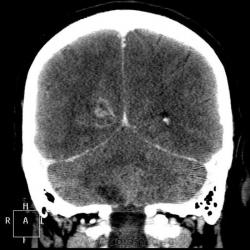

Мужчине 67 лет. У меня нет четкого мнения об изменении в правой затылочной доле. Ваше мнение?

"Непонятная штука в затылочной доле"-вероятнее артерио-венозная мальформация.Гиподенсная зона,прилежащая к ней-отдаленное последствие кровоизлиния из АВМ.

Может кавернома.

Склоняюсь к АВМ, прослеживается приводящий и отводящий сосуды. Не совсем понятно понижение плотности между сосудистыми петлями (может, коллега gar70 прав/а). Рекомендовала МРТ после выписки из сосудистого отделения (у нас такие вещи, что бы из сосудистых аномалий ни было, не оперируют).